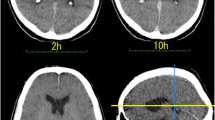

A total of ten CT image series (one series per subject) were acquired. In Fig. 1, we report two representative axial and sagittal planes obtained on the same subject at different times, namely 24 (a) and 114 (b) h after death. A qualitative analysis of Fig. 1a and b highlights a reduction in the LCV size and a change in its radiodensity. This finding is in close agreement with the results of Hasegawa and co-workers, which previously studied the time-dependent changes in LCV volume and radiodensity on three subjects between 2 and 24 hpm [11]. In this study, the authors found a linear decrease in the LCV volume associated with a linear increase in its radiodensity in the investigated postmortem interval. The results in Fig. 1a and b strongly suggest that the changes reported by Hasegawa and colleagues could continue even after 1 day from the clinical death, thus being of potential help in the estimation of the postmortem interval. However, the analysis of a single CT plane shown in Fig. 1 cannot be considered representative of the whole LCV changes; therefore – following Hasegawa et al. – we carried out a 3D segmentation of the entire LCV as described in material and methods, and we measured its volume and radiodensity over time up to approximately 270 hpm. Figure 1c–g summarize organically the segmentation process adopted to analyze the LCV, acquired from the PMCT images. As fully described in the Material and methods section, a segmentation algorithm implemented in the ImageJ software has been used to label the ventricle region, contouring and masking the related areas per single slice using image thresholding techniques; the steps of this process are depicted in Fig. 1c–e. A representative set of extrapolated masks of the ventricle slices are shown in Fig. 1f, and a representative three-dimensional reconstruction of the cerebral lateral ventricle after death is shown in Fig. 1g. This procedure has been repeated for each time point, for a total of ten available cases.

PMCT images in the axial (upper) and in the sagittal (lower) planes of the same representative brain slice at different times after death, namely 24 h (a) and 114 h (b). In c, a graphical representation of the input image set for the segmentation algorithm is shown; for each selected image, a contour (d) and a mask (e) of the ventricle region for each CT slice are shown. The extrapolated masks of the ventricle slices are represented (f), and three-dimensional reconstruction of the cerebral lateral ventricle is shown (g)